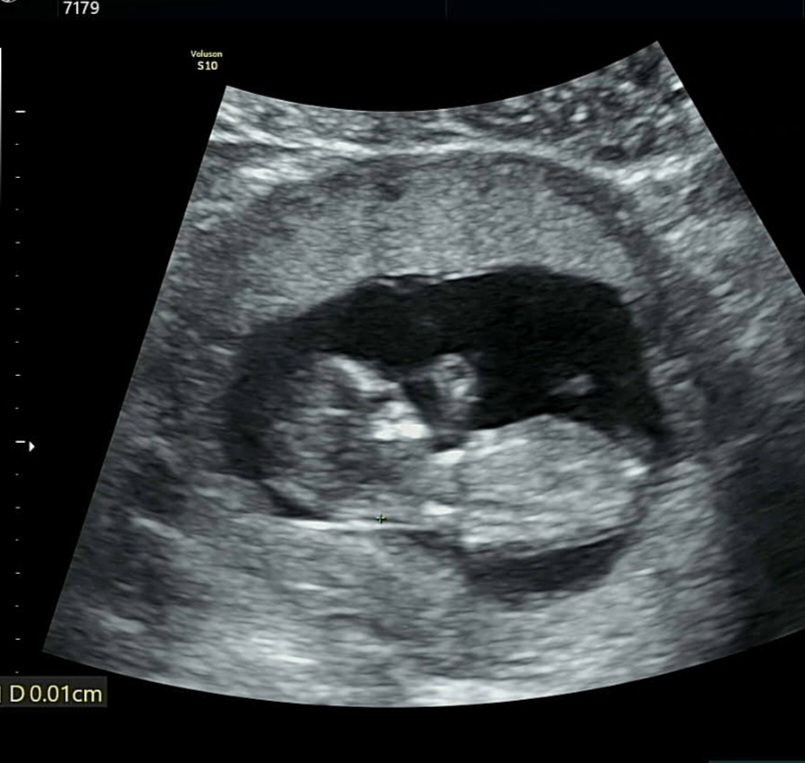

12주 3일 각도법 고수님들 도와주세요~

성별정확히 알려면 2주뒤에 와보라는데 너무 궁금해영 ㅠ

2주뒤에가야보이겟네요